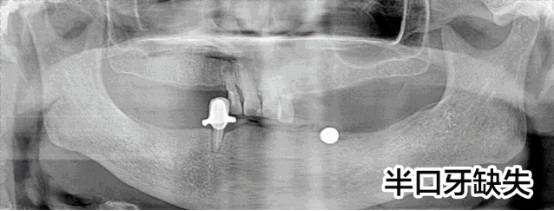

半口牙種植修復案例

病例簡介:周女士,女,57歲,家住泉州,因下半口牙在當地種植不成功而來我院就診。

劉斌元教授在為該患者做了詳細的檢查后表示:“周女士由于先前種植牙的失敗,造成對口腔牙槽的破壞比較嚴重,需要重新做手術修整牙槽”

決定種植方案后,劉斌元教授分別為周女士做了三次診療,第一次做電腦種植前準備;第二次做電腦種植手術,覆蓋義齒恢復;第三次做固定義齒修復。目前周女士的半口牙齒已種植完畢,果很好。